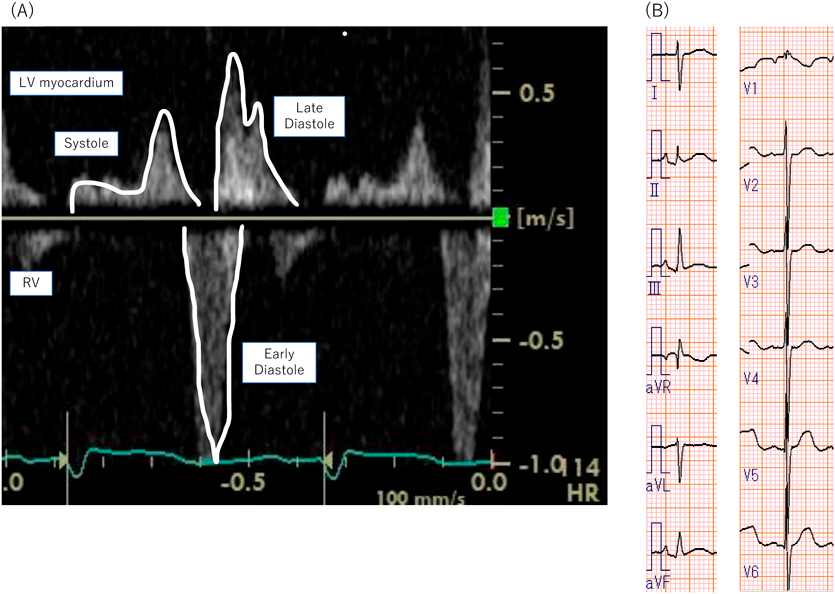

右室依存性冠循環を伴った右心低形成症候群に対する上行大動脈右室短絡術前後の冠血流評価Evaluation of Coronary Perfusion Using Pulsed-Wave Doppler in Hypoplastic Right Heart Syndrome with Right Ventricle-Dependent Coronary Circulation Before and After Aorta-To-Right Ventricle Shunt